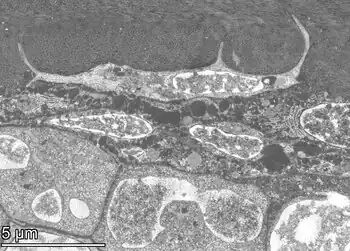

HAADF-STEM electron image of a maturing osteocyte (preosteocyte or osteoid osteocyte) at the bone surface, appearing directly above osteoblast-like precursor cells (decalcified matrix). Note the elongated cell processes that are surrounded by the collagen type I matrix and already crossing lamellar boundaries as collagen (and eventually mineral) continues to entomb the cell.